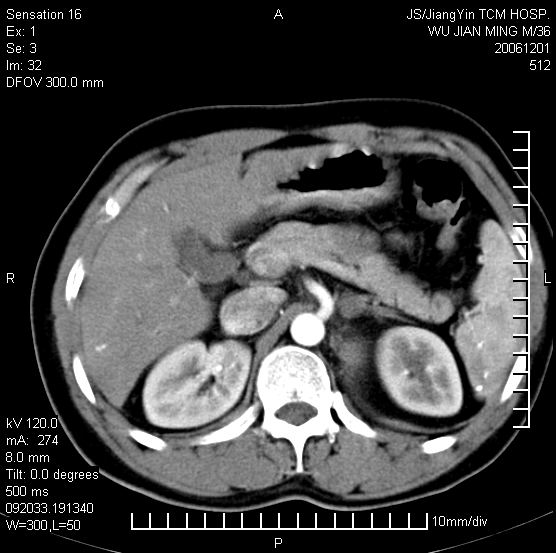

以下是引用dyqct在2006-12-1 21:17:00的发言:[br]左心缘旁及后肋膈窦区见巨大椭圆形混杂密度肿块,周围见大小不等斑片状钙化,内部无强化,周围包膜轻度强化,心脏明显受压变形,即明显占位效应,肿块广基与心包、膈相连。肝、脾内、肝门见多数小结节状钙化影。[br]考虑:1、左心缘旁及后肋膈窦区慢性包裹性胸膜炎(结核性);[br] 2、肝、脾及肝门淋巴结核已钙化。[br]

以下是引用zrs在2006-12-2 17:28:00的发言:[br]肺内、肝脾内虽有钙化,但不支持结核性胸胸膜炎包裹,而支持寄生虫感染![br][br]

以下是引用zyx168在2006-12-2 10:10:00的发言:[br][br]肝脾肺内多发钙化灶